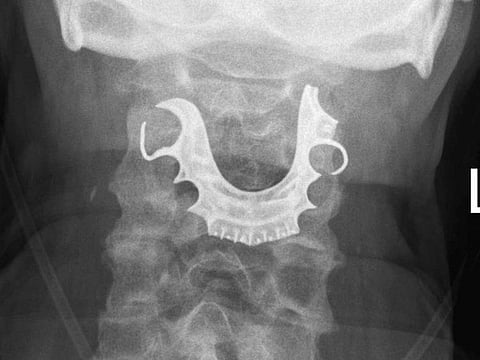

That's when a nasendoscopy - a fibre optic camera on the end of a tube inserted through a nostril - revealed a large, semicircular object covering his vocal cords.

"On explaining this to the patient, he revealed that his dentures had been lost during his general surgery eight days earlier, and consisted of a metallic roof plate and three front teeth," Cunniffe said.

The denture was removed surgically, and Jack was discharged six days later.